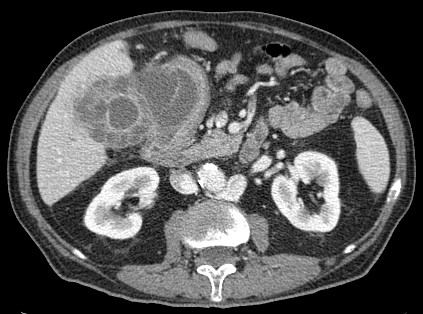

Se realiza ecografía abdominal:

En sucesivos cortes observamos lo siguiente:

Se observa una mala evolución radiológica. Dada la clínica del paciente y los hallazgos ecográficos podemos concluir que estos hallazgos son compatibles una colecistitis xantunogranulomatosa litiásica sobreinfectada (que se confirmó posteriormente con anatomía patológica).

- Colecistitis xantunogranulomatosa: nódulos o bandas intramurales. Se producen por la oclusión de los senos de Rokitansky Aschoff de la pared, los cuales se rompen, luego la bilis coloniza la pared y finalmente produce una reacción inflamatoria a la que puede sobreañadirse una infección. Es un factor de riesgo para el carcinoma.

- Eco y TC: Litiasis + engrosamiento mural focal o difuso. Puede haber cambios inflamatorios pericolecísiticos. Los nódulos hipocogénicos o bandas pueden sugerir el diagnóstico específico de c. xantunogranulomatosa.

- El diagnóstico raramente se realiza previo a la cirugía y al análisis histopatologíco.